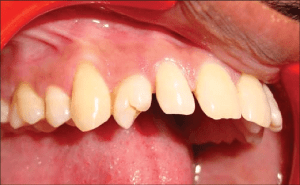

7. Transposition

One tooth in place of another